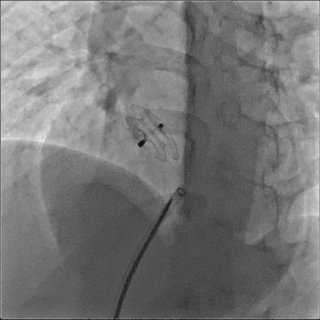

MemoPart™ devices from Lepu Medical form a family of self‑expanding transcatheter occlusion systems designed for minimally invasive closure of a variety of congenital and structural heart defects. These include closure devices for Patent Foramen Ovale (PFO), intended to seal paths associated with stroke or transient ischaemic attacks; Atrial Septal Defect (ASD) occluders for the correction of atrial septal defects; Ventricular Septal Defect (VSD) occluders available in muscular and membranous types; and Patent Ductus Arteriosus (PDA) occluders for percutaneous closure of persistent ductus arteriosus. Each device typically features a self‑expanding double‑disc or mesh structure tailored to the specific anatomy of the defect, aiming to provide secure occlusion, high biocompatibility and visibility under fluoroscopy during implantation.